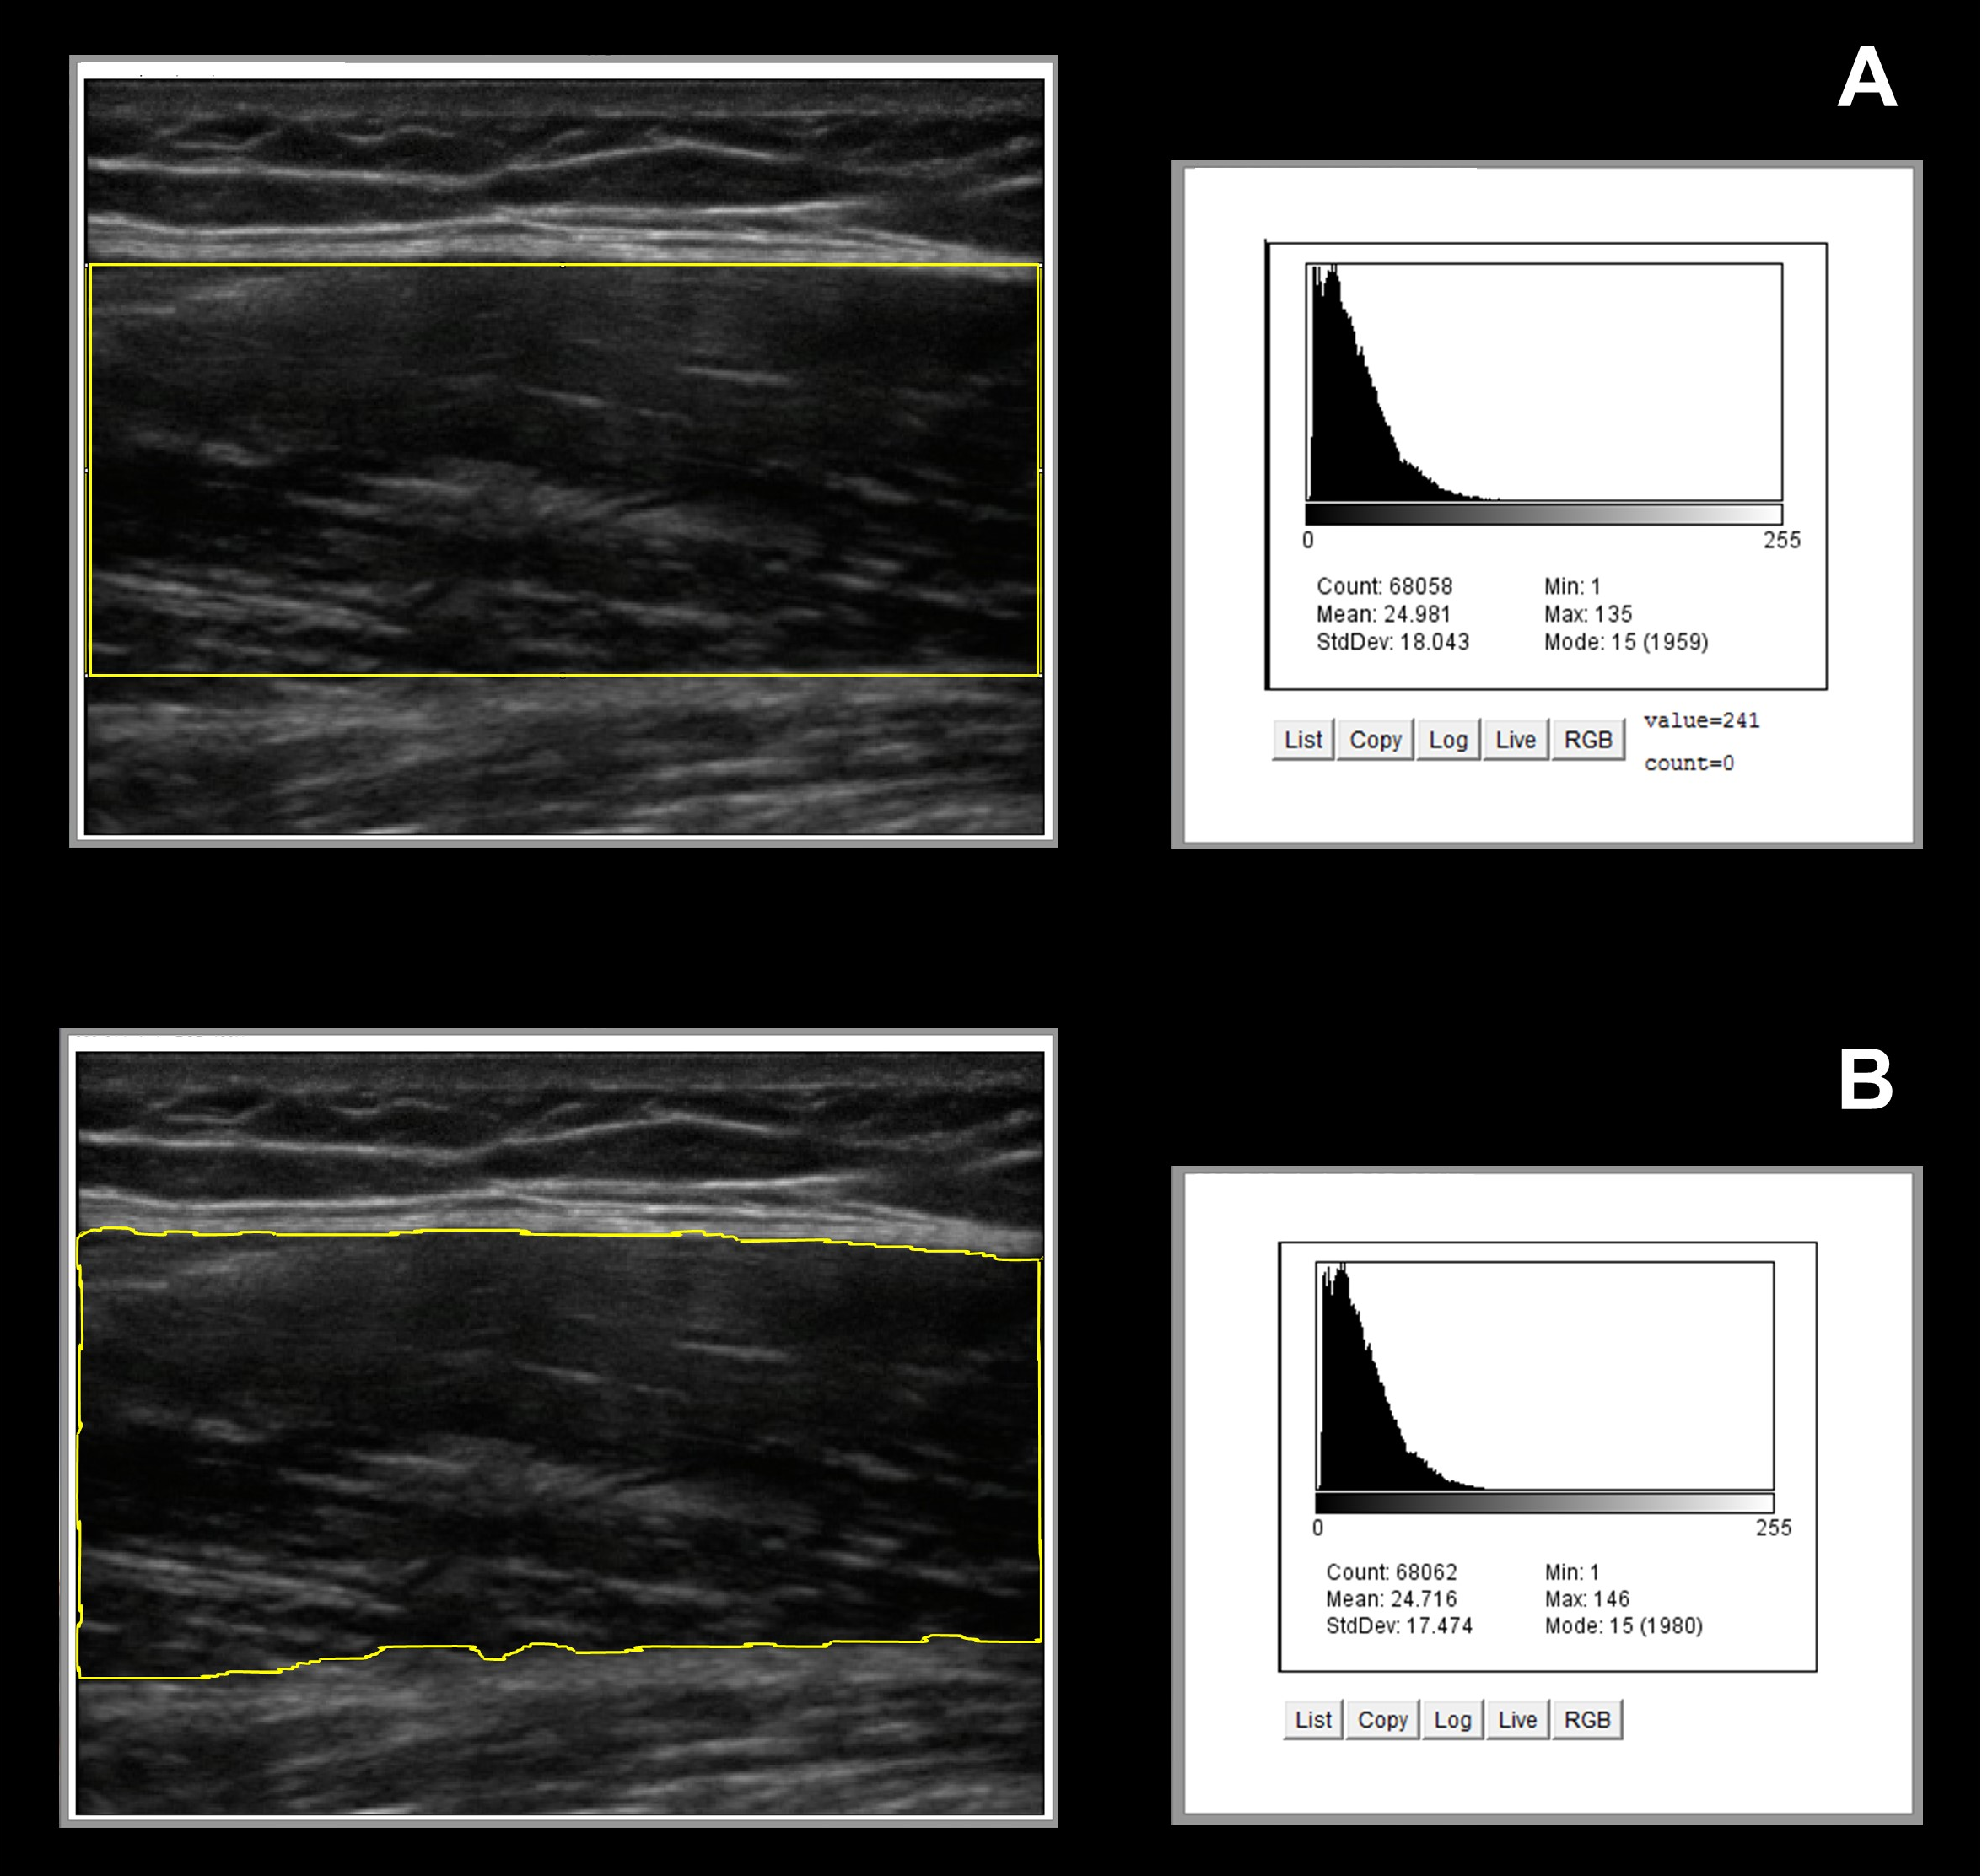

En mujeres jóvenes o aquellas con senos densos, el tejido mamario puede dificultar la visibilidad de algunas masas en una mamografía. Sin embargo, el ultrasonido mamario proporciona una visión más clara de los tejidos densos y puede detectar lesiones que no son visibles en las radiografías. Esto es especialmente importante para identificar cambios tempranos en los senos que podrían pasar desapercibidos en otros exámenes.

El ultrasonido mamario tiene una eficacia notablemente alta en mujeres jóvenes, especialmente aquellas menores de 40 años, debido a la densidad de su tejido mamario. El tejido mamario denso puede enmascarar la presencia de tumores pequeños en una mamografía, lo que disminuye la eficacia de este procedimiento en mujeres más jóvenes. En cambio, el ultrasonido es capaz de proporcionar imágenes más detalladas y claras en estos casos, lo que lo convierte en una herramienta preferida en la detección de enfermedades mamarias en esta población.

Estadísticas de Eficacia en la Detección Temprana

El ultrasonido mamario ha demostrado ser una herramienta eficaz para detectar cáncer de mama en etapas tempranas, lo que es crucial para un tratamiento exitoso. Según un estudio de la Sociedad Americana del Cáncer, el ultrasonido mamario tiene una tasa de sensibilidad del 85% en la detección de masas sólidas en mujeres con senos densos. Esto significa que el ultrasonido puede detectar la mayoría de los tumores presentes, lo que permite iniciar un tratamiento lo antes posible.